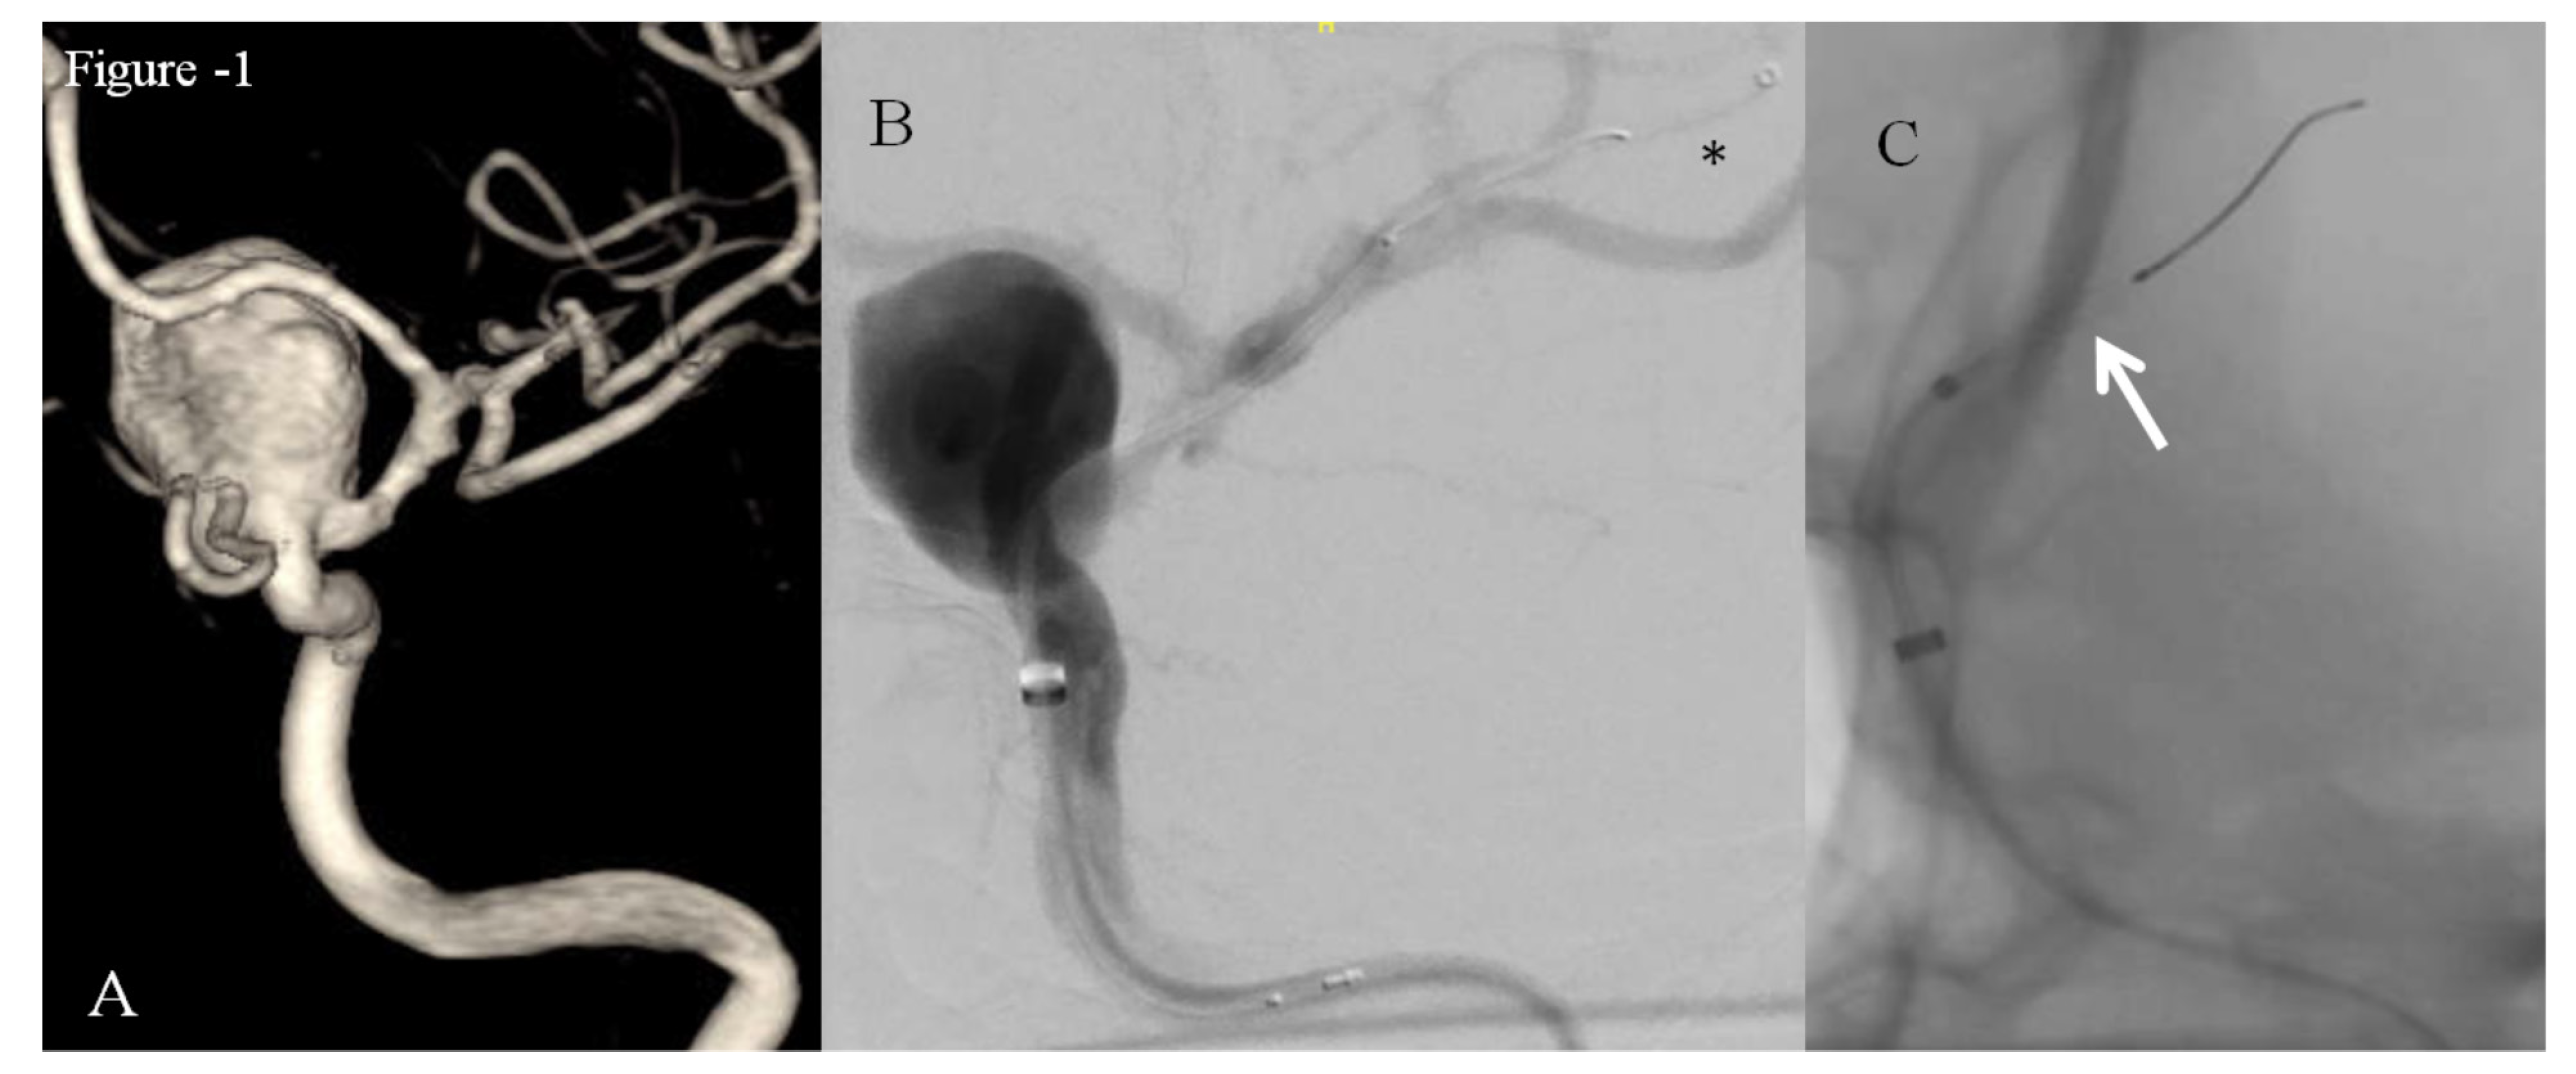

1. After deployment of the Pipeline stent, we encountered many difficulties trying to recapture the delivery wire while attempting to resheath it. It took a moment to realize that the distal tip of the catheter had gotten stuck between the distal marker and the polytetrafluoroethylene (PTFE) sleeve. Meanwhile, we applied reasonable pull force and maneuvered the catheter to recapture the delivery wire (Figure 2).

2. Wire fracture proximal to the proximal marker was recognized by the inability to navigate and the unresponsiveness of the distal delivery wire during torquing and subsequent withdrawal of the wire (Figure 3).

4. Microsnare (Amplatz Goose Neck Snare Kit, comprising 4 mm Loop Snare with true 90° angle, 2.3-3.0 Fr Goose Neck snare catheter) was inserted to pull out the fractured wire by snaring, but was not successful.

5. Subsequently, a Hyperglide balloon catheter (Medtronic) was advanced through the intermediate catheter and placed distal to the resheathing marker of delivery wire. The entire system was pulled out successfully by sandwiching the delivery wire between the inflated balloon and intermediate catheter lumen (Figure 2 and Figure 4).